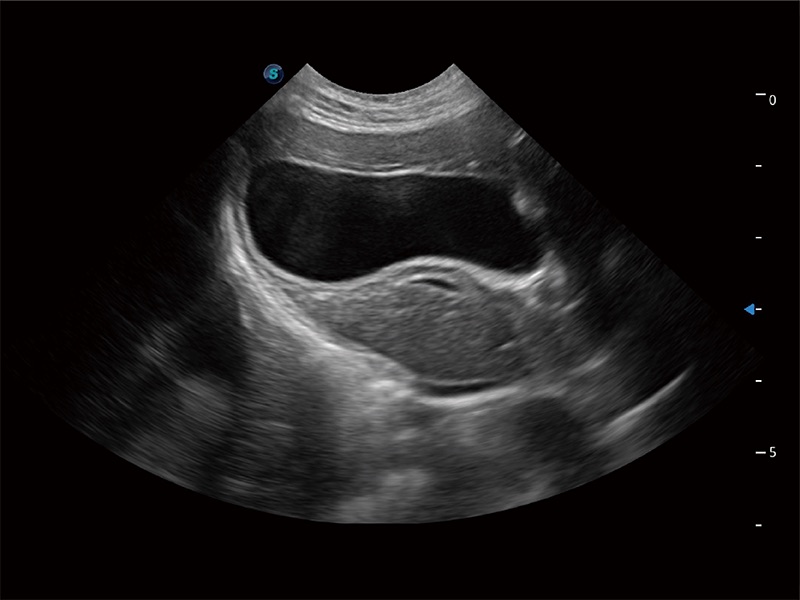

一键自动识别膀胱壁及自动测量膀胱容积,不受膀胱形状和大小的限制,帮助医生快速精准获得测量的数据。

高性能和先进的临床应用工具可以为动物医生提供临床信心。ProPet 80 搭载了先进的腹部和浅表应用工具,帮助医生在日常临床实践中发挥前所未有的作用。

ProPet 80 专为动物医生设计,对不同的动物体型和生理结构作出了针对性的优化。通过动物影像专用软件,可满足个性化的应用需求,帮助动物医生获得更精确的诊断数据。